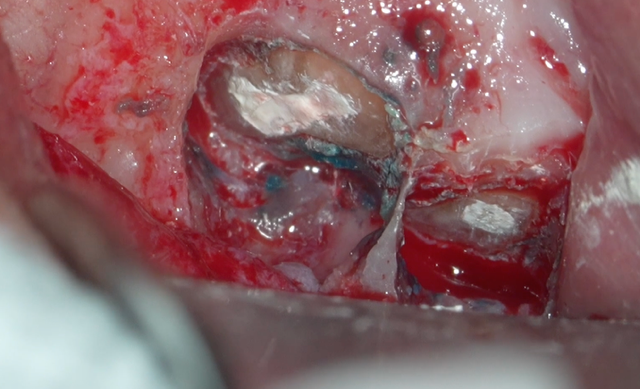

歯根の先端 約3mmを切断

根の先を切るだけでは治りません。

その内部の感染を取り除く処置(逆根管形成)がとても重要になります。

これにより、根管内部の細菌数を減らしています。

逆根管充填🟰しっかりと封鎖